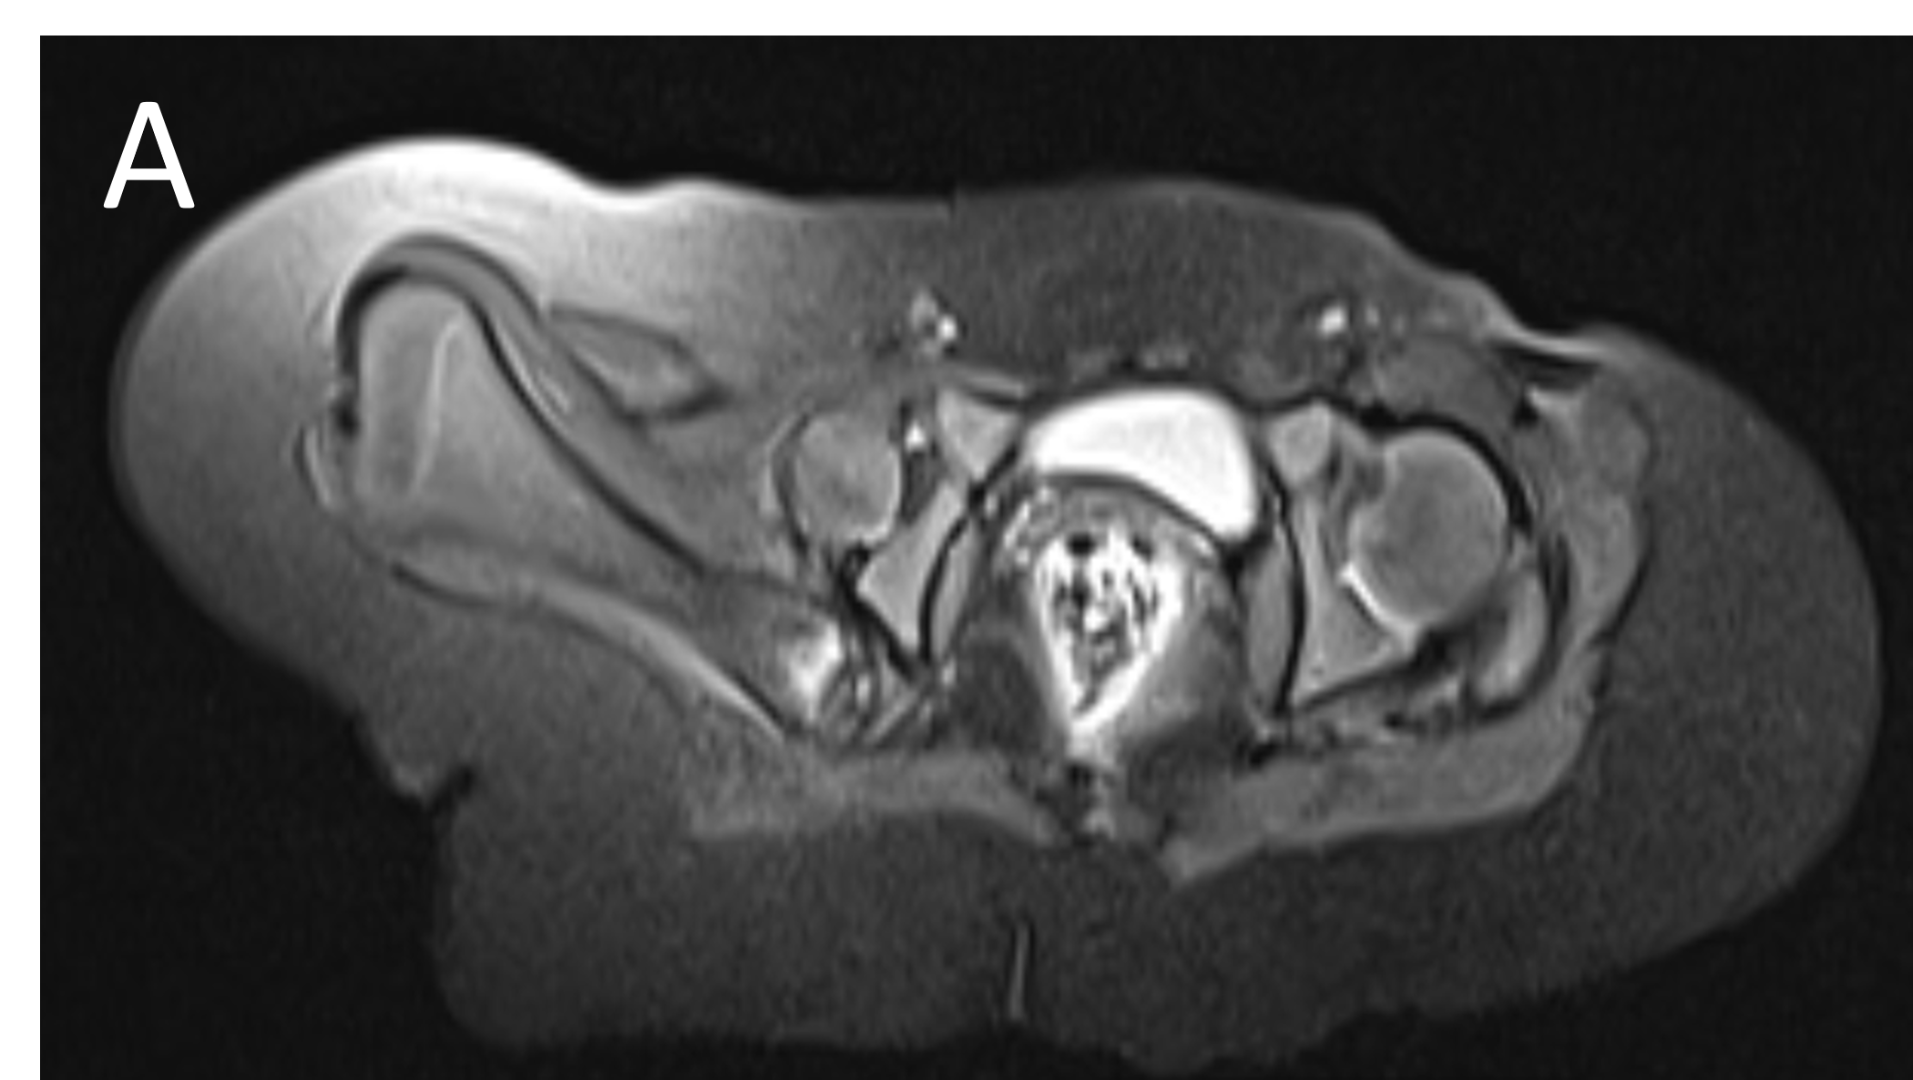

An 18 month old baby presented with hip deformity – MRI bilateral hips was advised

- A.LEGENDS – MR BILATERAL HIPS :Right femur is shortened, with a coxa vara deformity. Femoral shaft measures 7.2 cm in length. The acetabulum is moderately dysplastic and anteriorly rotated, But contains the femoral head. The femoral head and neck appear hypoplastic and posteriorly and externally rotated.

- B.LEGENDS – MR BILATERAL HIPS : Generalised atrophy of muscles of thigh and gluteal region on the right compared to the left.

PROXIMAL FOCAL FEMORAL DEFICIENCY

Bilateral Proximal focal femoral deficiency (class B on right side and class C on left side).